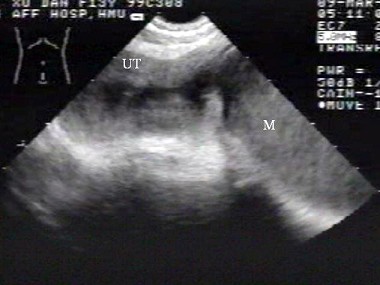

[单选题]女性,62岁,1周前疑诊为宫颈癌。超声检查如图,最可能的诊断是()A .子宫肌瘤B .宫腔积液并感染C .子宫内膜癌D .子宫内膜炎E .正常声像图

[单选题]女性,62岁,1周前疑诊为宫颈癌。超声检查如图,最可能的诊断是()A . 子宫肌瘤B . 宫腔积液并感染C . 子宫内膜癌D . 子宫内膜炎E . 正常声像图

[单选题]女性,62岁,1周前疑诊为宫颈癌。超声检查如图,最可能的诊断是()。A . 子宫肌瘤B . 宫腔积液并感染C . 子宫内膜癌D . 子宫内膜炎E . 正常声像图